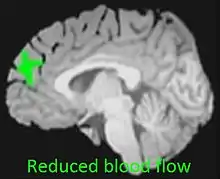

Cannabis users have shown decreased reactivity to dopamine, suggesting a possible link to a dampening of the reward system of the brain and an increase in negative emotion and addiction severity.[8]